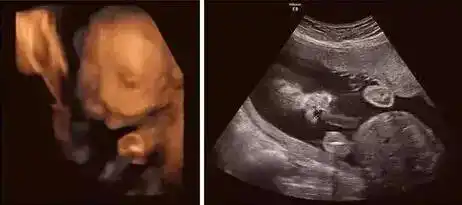

问答 怀孕期 树友ph8gu04n孕22周6天2016-10-13 推荐回答

1.2三维超声显示单侧唇裂.

双胎宝妈21周做四维彩超,筛查出一名胎儿为"唇腭裂"

夫妻俩都很高兴,然而,22周的时候,做大排畸检查,医生说宝宝唇裂,建议

想知道宝宝是否健康 超声影像(四维彩超) 针对22—28周之间的宝妈